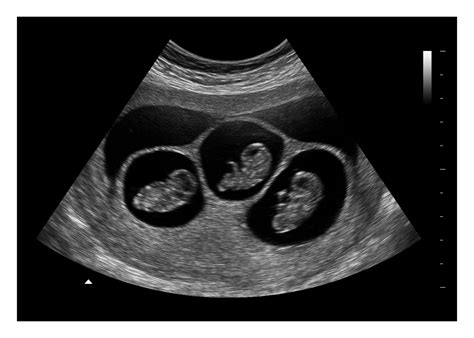

At 8 weeks, the fetus is still very small, but several key structures can be visualized:

• Gestational Sac: A fluid-filled structure that contains the developing embryo.

• Yolk Sac: A small, round structure that produces blood cells and helps in the early development of the embryo.

• Embryo: The developing fetus, which is about the size of a raspberry at this stage.

• Fetal Heartbeat: A rapid heartbeat, usually between 120 and 160 beats per minute, can be detected.

• Amniotic Sac: The sac that contains the amniotic fluid, which cushions and protects the fetus.

While the fetus is still too small to see detailed features, the presence of these structures is a positive sign of a healthy pregnancy.